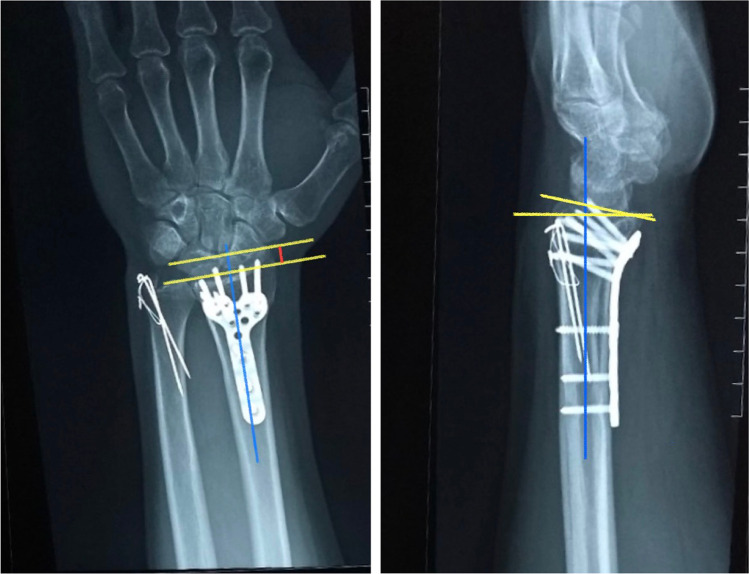

Clinical and radiographic re-evaluation was done every three months for uneventful cases including subjective clinical outcomes (Mayo, and Q-DASH scores, the validated Arabic form was used), objective clinical outcomes (wrist ROM and grip strength), and measuring radiographic parameters (radial height and volar tilt) (Figs. 4 and 5). Cases that developed any complaints during the follow-up period had a more frequent assessment.

Fig. 5.

Radial height and volar tilt measured in a case fixed with a variable-angle volar locking plate